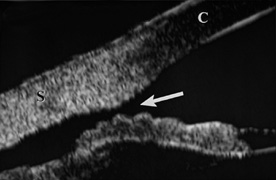

When the cornea is abruptly forced backward by severe blunt trauma, it presses the iris against the lens, preventing the escape of aqueous into the posterior chamber. If enough force is applied, the entrapped aqueous dissects into the ciliary body, resulting in a recessed angle (Fig. 4). This tearing of the ciliary body is responsible for approximately 90% of the hyphemas seen after blunt trauma.31,32 Other causes of hemorrhage include separation of the iris from the ciliary body (iridodialysis) and sphincter tears. Ultrasound biomicroscopy can be useful in diagnosing dissection of the ciliary body or iridodialysis (Fig. 5).33–35

Fig. 4. Angle recession after blunt trauma.

Fig. 5. Ultrasound biomicroscopy image of cyclodialysis (arrow). “C” identifies the cornea, “S” identifies the sclera.